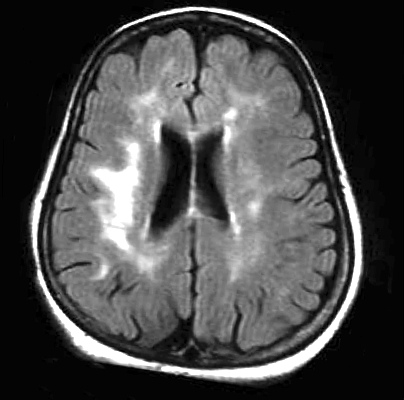

La progressió de la leucoaraiosi tendeix a seguir un patró general. Inicialment s’observen les lesions periventriculars a la zona del marge (barrets) dels ventricles laterals (Fig. 1) estenent-se, en relació amb la severitat del fenomen, al voltant d’ells (Fig. 2).

Tal com hem esmentat, la Leucoaraiosi es refereix a unes alteracions que es poden detectar mitjançant les imatges de la Tomografia Axial Computada (TAC) i per Ressonància Nuclear Magnètica (RM) cerebral, que consisteixen en zones d’hipodensitat o d’hiperintensitat, respectivament.

Entre les dues, la Imatge per RM de l’encèfal (IRM) que inclou seqüències ponderades en T2 i FLAIR, és la tècnica més estesa en la valoració de la Leucoaraiosi.